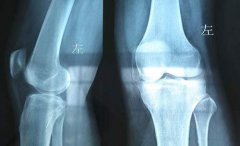

来自许昌市禹州的赵先生来到我院(郑州痛风风湿病医院)进行治疗,自述37岁时出现双膝关节游走性疼痛,吃止痛药后疼痛缓解,再次发作时疼痛加重吃药无效,去医院检查后确诊风湿性关节炎。药物治疗三年来,膝关...[详细]

来自开封市鼓楼区62岁的吴阿姨来到我院(郑州痛风风湿病医院)进行检查,被风湿性关节炎折磨了八年的吴阿姨显得异常憔悴。膝关节肿胀疼痛令她无法正常下地行走,需要坐在轮椅上生活。2018年在儿子的带领下,来...[详细]